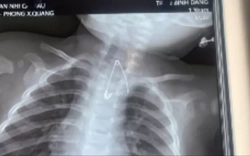

• Đang ăn sữa chua, người phụ nữ nuốt chiếc thìa dài 17cm vào bụng

Đang ăn sữa chua, người phụ nữ nuốt chiếc thìa dài 17cm vào bụng

Sức khỏe -

Một người phụ nữ đã vô tình nuốt phải một chiếc thìa dài 17cm khi con chó của cô nhảy lên đùi trong lúc cô đang ăn sữa chua.